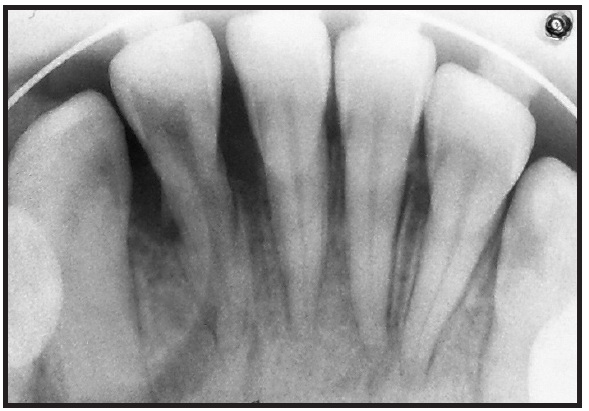

To unlock the occlusion, glass-ionomer-cement bite planes were bonded to the occlusal surfaces of the upper first molars. The archwire series consisted of flexible .016", .018", and .020" round coaxial wires, followed by preformed .016" and .018" round stainless steel wires. After five months of treatment, the mobility of the lower right lateral incisor persisted, despite the elimination of the traumatic occlusion (Fig. 3). Periodontal probing of the tooth's labial root surface revealed EIRR, which was confirmed with an occlusal radiograph (Fig. 4).

Fig. 4 External inflammatory root resorption (EIRR) of lower right lateral incisor.

Orthodontic tooth movements are facilitated by osteoclastic resorption of the alveolar bone facing the periodontal ligament, so that the roots move in the direction of the applied force.26 This area of compressed tissue, which often becomes necrotic, also contains the multinucleated odontoclasts involved in root resorption.18 The orthodontic movement of the lower lateral incisor shown here was a linguoversion (rotational movement around the center of rotation, located at about the middle of the root). Such a force application would compress the periodontal ligament facing the lingual surface of the root above the center of rotation, as well as the labial surface below the center of rotation, promoting resorption of the alveolar bone in those areas. Any EIRR caused by the orthodontic forces should therefore have been evident on the lingual root surface above the center of rotation and on the buccal root surface below the center of rotation, facing the compression zones of the periodontal ligament. In actuality, however, we observed EIRR on the labial surface above the center of rotation of the right lateral incisor. Therefore, the root resorption was more likely attributable to the pretreatment occlusal trauma than to the orthodontic forces used.